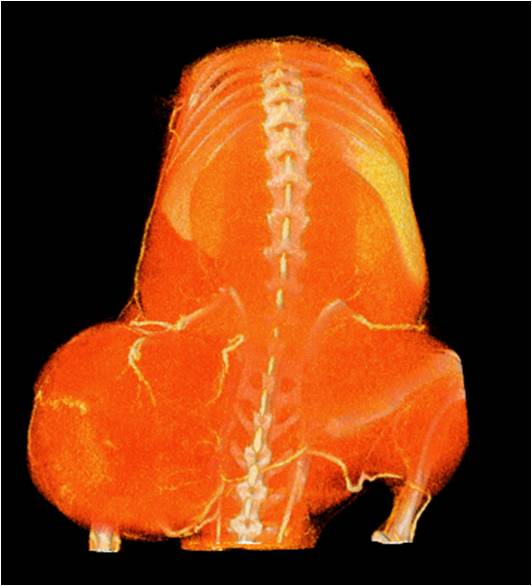

ChiPet 100是一款針對離體骨,小鼠,大鼠及兔子等動(dòng)物進(jìn)行多功能3D掃描的Micro-CT系統。

可以測量骨參數、棕色脂肪、皮下脂肪、脂肪肝、血管、腫瘤轉移等參數。

• 能進(jìn)行骨相關(guān)研究成像,包括關(guān)節炎、骨質(zhì)疏松、骨損傷修復、骨再生等領(lǐng)域,可進(jìn)行骨密度、骨微結構、骨小梁的定量分析;

• 能進(jìn)行脂肪研究成像,能夠分離出皮下脂肪、內臟脂肪、棕色脂肪,并對脂肪體積含量進(jìn)行定量測定;

• 能進(jìn)行呼吸道研究成像,獲取正?;蚣膊顟B(tài)時(shí)肺部及支氣管影像,并對體積等參數進(jìn)行定量分析;

• 能進(jìn)行心臟研究成像,包括心梗、心肌肥大、動(dòng)脈粥樣硬化、心臟血管病變等研究,可獲取舒張期及收縮期心臟體積參數及左心室射血分數等功能參數;

• 能進(jìn)行全身血管成像研究,獲得高分辨率的血管造影影像;

• 能進(jìn)行肝、脾、腎等內臟的成像研究,獲得體積、表面積等定量參數。